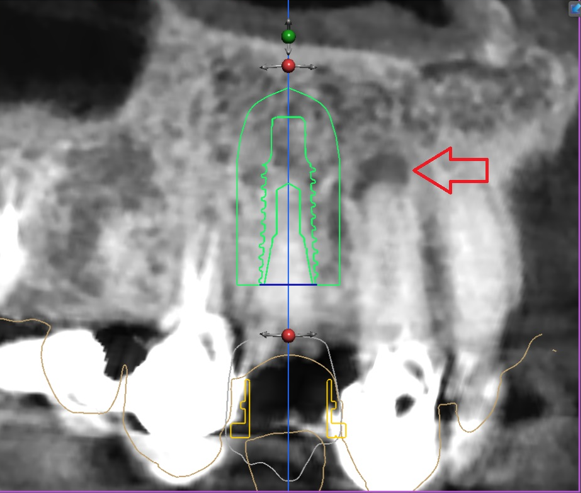

디지털 임플란트 진단을 하면서,

apical lesion(뿌리 염증) 이 있는것이 관찰이 되며

당일 발치 후 즉시식립을 하기로 했습니다.

근데.. 이미 치조골이 많이 얇죠?

이렇게, 얇은 뼈에 임플란트를 심으려니,

정확한 진단을 해야 됩니다.

그래서, 위에서 볼 수 있는 사진들 처럼

여러가지 방법을 동원하여 현 상황을

정확히 분석을 해야 되겠죠.

좁은 치조골 및 폭경이 충분하질 않았으며,

3개씩이나 되는 implant fixture 들을

한번에 심어야 되는데.. 그것도 나란히요.